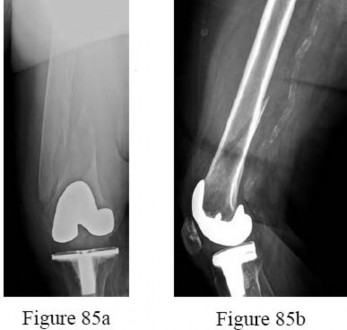

Figure 64 is the radiograph of a 77-year-old woman with a painful total hip arthroplasty (THA) who had surgery 15 years ago. Preoperative laboratory studies reveal a C-reactive protein (CRP) of 4 mg/L(reference range, 0.08-3.1 mg/L). Her serum white blood cell (WBC) count and differential values are within defined limits, and her erythrocyte sedimentation rate (ESR) is 35 mm/h (reference range, 0-20mm/h).

What is the next appropriate step in management of the patient?

Explanation

Aspiration is appropriate in the setting of a failed total joint replacement when ESR and CRP are elevated,even with a normal systemic WBC count. A MRI scan of the hip is not useful in this setting. A labeled WBC scan is of no additional value when an aspiration of the hip is planned. Although multiple cultures should be obtained at the time of revision THA, preoperative aspiration is appropriate in this case. Most acetabular revisions can be accomplished with a cementless hemispherical component.

Supplemental fixation with screws is indicated. In this patient, the acetabular rim and columns are intact and the first choice is a cementless hemispherical component. Bilobed components have an unacceptably high failure rate and are not indicated when the acetabular rim is intact. A cemented all-polyethylene shell is not likely to achieve adequate long-term fixation with the sclerotic acetabular bone. An antiprotrusio device is indicated in the setting of severe bone loss or pelvic discontinuity. An antiprotrusio cage is the best choice in the setting of a pelvic discontinuity that has the capacity to heal. If the discontinuity does not have the capacity to heal, it can be treated in distraction with an acetabular allograft supported by a cage or custom triflange component. A large porous cup is not likely to achieve stable fixation and will require removal of more acetabular bone. A cemented acetabular component will not achieve adequate stability or fixation in the absence of additional support. Resection arthroplasty would not be the first choice in a potentially reconstructable situation. PREFERRED RESPONSE: 3